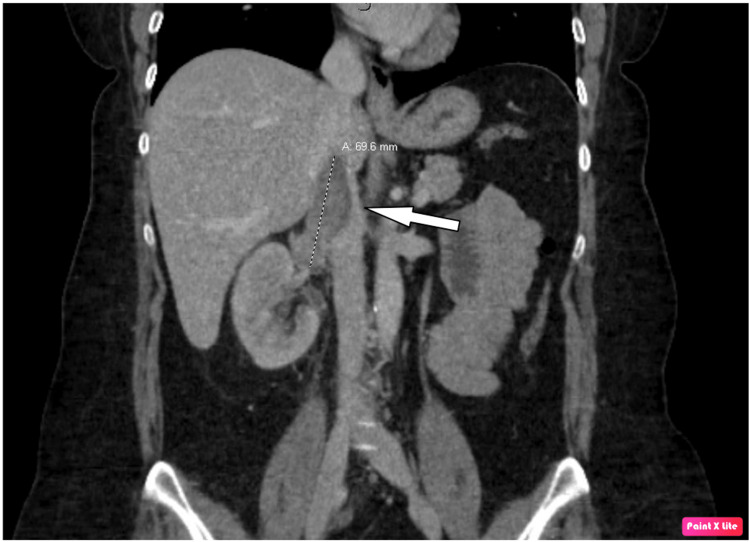

The patient is a 48-year-old Caucasian female who presented to the emergency room (ER) with acute right flank pain and hematuria. Computed tomography (CT) of the abdomen and pelvis showed a right renal mass with extension to the inferior vena cava (IVC) (Figure 1) and retroperitoneal lymphadenopathy.

Figure 1. CT of the abdomen and pelvis showing a right renal mass with inferior vena cava extension (white arrow).

CT: computed tomography